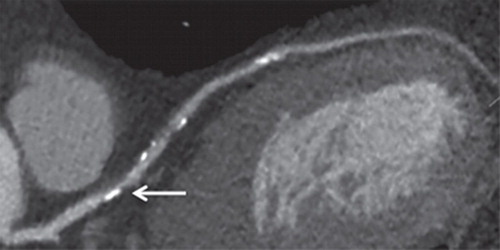

Manejo de la hipertensión en pacientes con comorbilidades cardiovasculares

Las guías recomiendan terapias de combinación doble y triple usando bloqueadores del sistema renina-angiotensina, bloqueadores de los canales de calcio y/o un diuréticoDependiendo de las comorbilidades, se deben preferir algunos medicamentos mientras que otros están contraindicados. Se está investigando la denervación renal con catéter (indicada por la lupa) para pacientes con hipertensión y comorbilidades asociadas con una mayor actividad del sistema nervioso simpático. European Heart Journal, 7 noviembre 2022